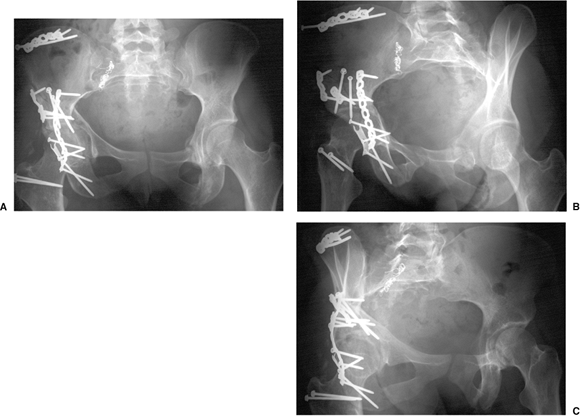

use of fluoroscopy is essential to assure the adequacy of reduction and

the position of the fixation (Fig. 43.17).

Figure 43.17. Patient from Figures 43.3 and 43.6 at 1-year follow-up. Congruent reduction and maintenance of joint space is shown. A. AP pelvis. B. Iliac oblique view. C. Obturator oblique view.

pelvis and 45-degree oblique Judet views) and a CT scan to assess

critically the fracture reduction and hardware position. The CT scan is